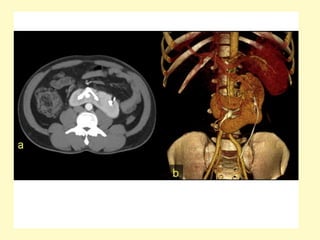

Ectopic pelvic kidney, Volume rendering (a) demonstrates absence of the left

kidney at the left renal fossa, instead, an ectopic left pelvic kidney is seen,

the axial contrast-enhanced MDCT image (b) shows an engorged left iliac

vein (asterisk), due to left aberrant renal vein (not shown), the ectopic

kidney receives blood supply from two renal arteries arising form the aorta

(arrowhead) and left iliac artery (arrow)